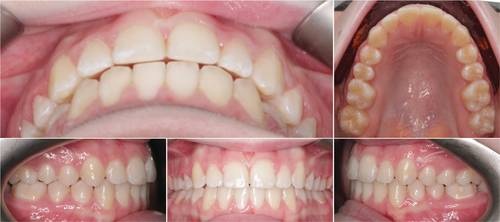

Fig. 2: Pretreatment intraoral photographs

Ruby, a 14-year-old female patient, presented with crowding of the upper incisors, Class II malocclusion, over-retained primary second molars, a midline discrepancy, and narrow arch forms (Figs. 1–3). We initiated treatment using the LightForce system, combined with remote monitoring through DentalMonitoring.